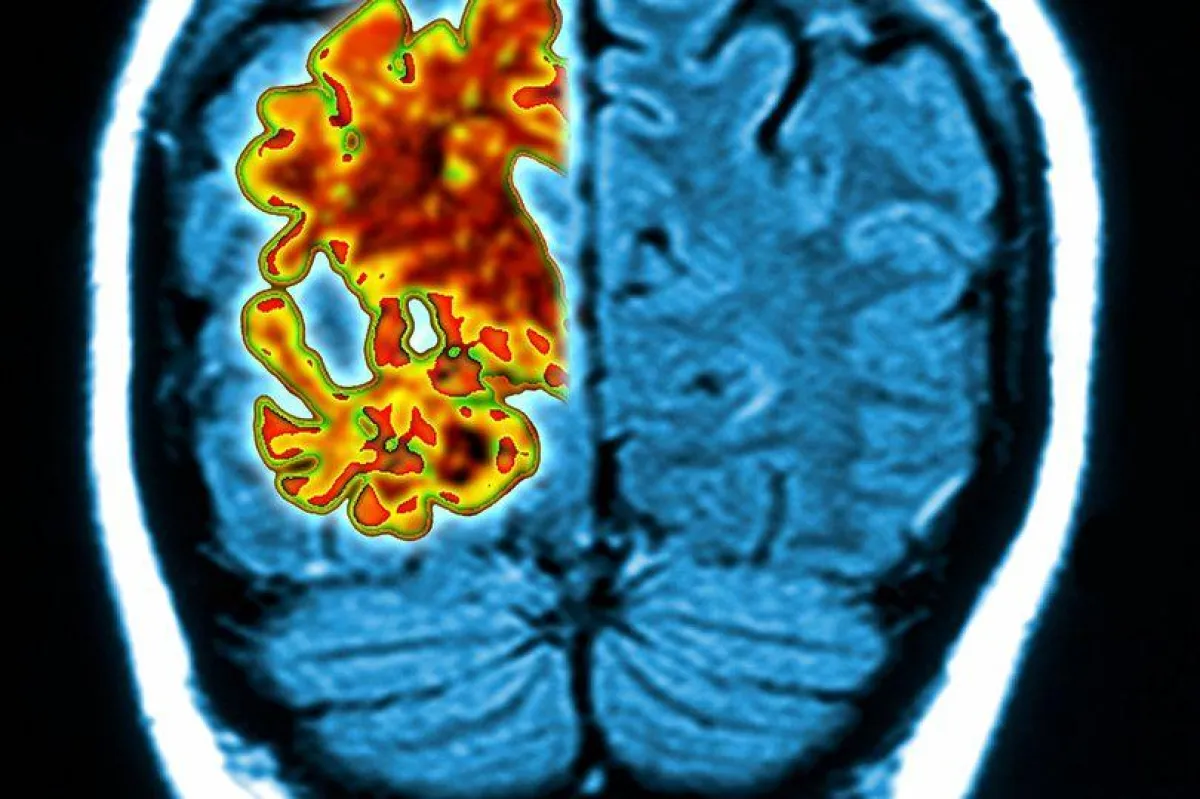

توصل علماء من جامعة واشنطن باختبار عينة للدم لتشخيص مرض الزهايمر قبل عقدين من حدوث أعراضه.

وبحسب موقع «ميرور» يقيس الاختبار البسيط مستويات البروتين المرتبطة بالمرض في الدم وتبين أنه دقيق بنسبة 94%.. فقبل أن يتطور فقدان الذاكرة والارتباك، تتراكم كتل البروتين «أميلويد بيتا» في أدمغة المصابين بالمرض.

كان اختبار الدم لتشخيص الخرف هو الهدف الأساسي لعلماء الأعصاب، لأن معالجة المرض قبل بدء الأعراض الأمر الذي كانوا يسعون إليه لأنه بمجرد أن يتطور الضرر فلا يمكن إصلاح ما قد تلف بالفعل في الدماغ.. ويمكن أن يكون الاختبار، الذي طوره باحثون أمريكيون من جامعة واشنطن، متاحاً للأطباء في غضون بضع سنوات.

ذكر الباحثون أنهم يستطيعون قياس مستويات البروتين في الدم واستخدامها للتنبؤ بما إذا كان «أميلويد بيتا» قد تراكم أم لا.. وعندما يتم دمج نتيجة هذا التراكم مع اثنين من عوامل الخطر الرئيسية لمرض الزهايمر - العمر ووجود البديل الوراثي APOE4 - سيتم التعرف على الأشخاص الذين يعانون من تغيرات مبكرة في الدماغ بدقة 94%.